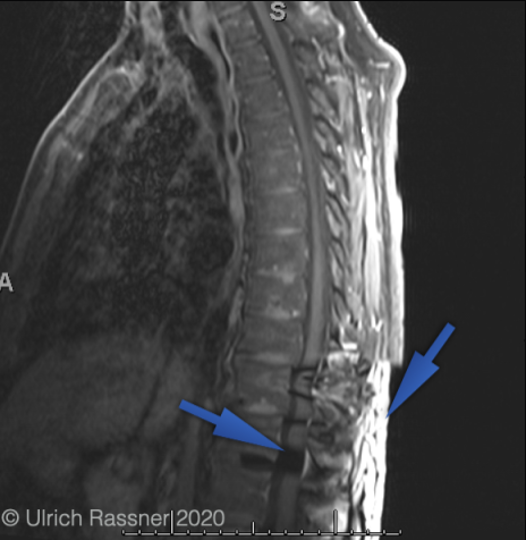

k-space data error (herringbone)

A single erroneous data point (spike) in k-space creates a line pattern through the image

if data point is on the x-axis the lines will be verticle, if the data point error is on the y-axis the lines will be horizontal. If the lines are diagonal, the data error is not on an axis.

how to fix: Repeat the scan without parameter changes (usually due to random error). But, if it occurs frequently as faulty coil may be the problem

k-space data error (herringbone artifact)

Due to a data flitch/ reconstruction error

To fix this just reconstruct again and hopefully the error in k-space will resolve